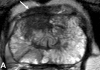

Prostate cancer is a common cancer in men and continues to be a major health problem. Imaging plays an important role in the clinical management of patients with prostate cancer. An important goal for prostate cancer imaging is more accurate disease characterization through the synthesis of anatomic, functional, and molecular imaging information. Positron emission tomography (PET)/computed tomography (CT) in oncology is emerging as an important imaging tool. The most common radiotracer for PET/CT in oncology, (18)F-fluorodeoxyglucose (FDG), is not very useful in the imaging of prostate cancer. However, in recent years other PET tracers have improved the accuracy of PET/CT imaging of prostate cancer. Among these, choline labeled with (18)F or (11)C, (11)C-acetate, and (18)F-fluoride has demonstrated promising results, and other new radiopharmaceuticals are under development and evaluation in preclinical and clinical studies. Large prospective clinical PET/CT trials are needed to establish the role of PET/CT in prostate cancer patients. Because there are only limited available therapeutic options for patients with advanced metastatic prostate cancer, there is an urgent need for the development of more effective treatment modalities that could improve outcome. Prostate cancer represents an attractive target for radioimmunotherapy (RIT) for several reasons, including pattern of metastatic spread (lymph nodes and bone marrow, sites with good access to circulating antibodies) and small volume disease (ideal for antigen access and antibody delivery). Furthermore, prostate cancer is also radiation sensitive. Prostate-specific membrane antigen is expressed by virtually all prostate cancers, and represents an attractive target for RIT. Antiprostate-specific membrane antigen RIT demonstrates antitumor activity and is well tolerated. Clinical trials are underway to further improve upon treatment efficacy and patient selection. This review focuses on the recent advances of clinical PET/CT imaging and RIT of prostate cancer.